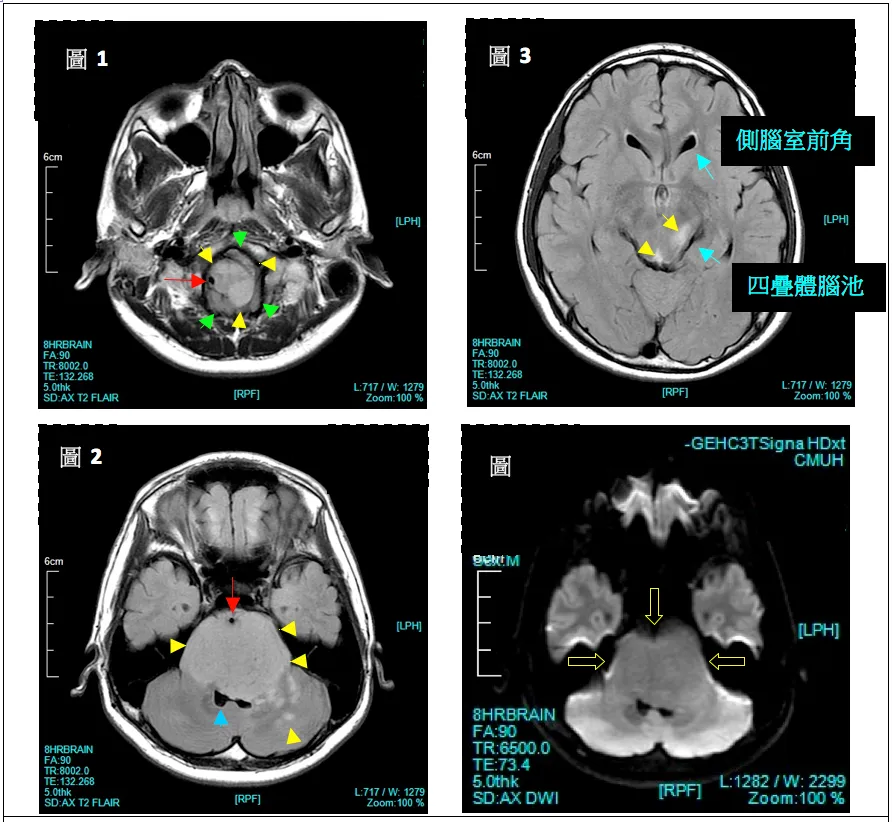

影像学MR解析

整个脑干(延髓、脑桥、中脑)在T2WI上呈现信号增强病灶(黄色箭头)。脑室系统虽受压变形,但未出现脑室扩大或脑积水情形(蓝色箭头)。肿瘤核心位于脑桥中心,出现时可占据轴向直径50%以上,通常包绕基底动脉。尽管DIPG沿纤维束浸润性和弥漫性生长至邻近位置,但很少转移至远处。

Fig.1:病灶使脑桥扩大,疑似向外突出小外凸物(绿色箭头)。病灶紧邻右椎动脉(红色箭头)。

Fig.2:显示整个脑桥充满高信号灶,脑桥体积增大但形状大致不变。基底动脉被肿瘤包围并前推(红色箭头),第四脑室受压,左侧尤甚(蓝色箭头),肿瘤扩散至小脑。

Fig.3:显示中脑也出现增强信号。